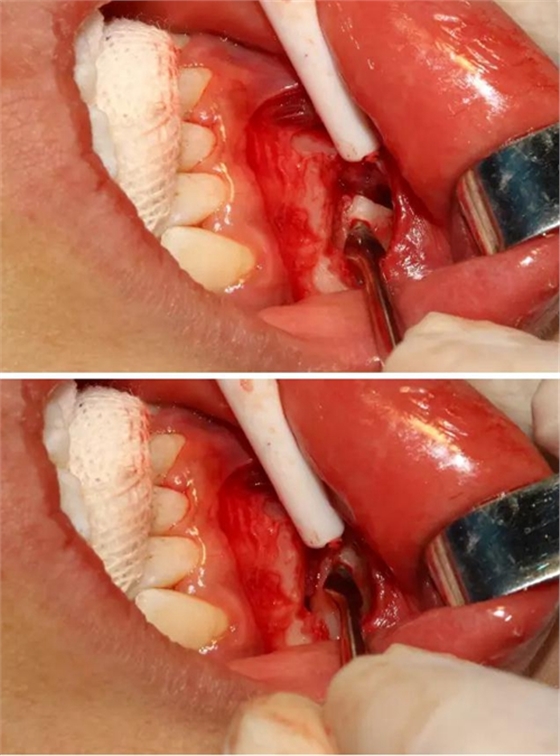

同時在剩余的根部斷面4MM下,預備2MM的溝槽,通過剝離子的三角尖端將牙體推出

三彎探針取出牙根部分